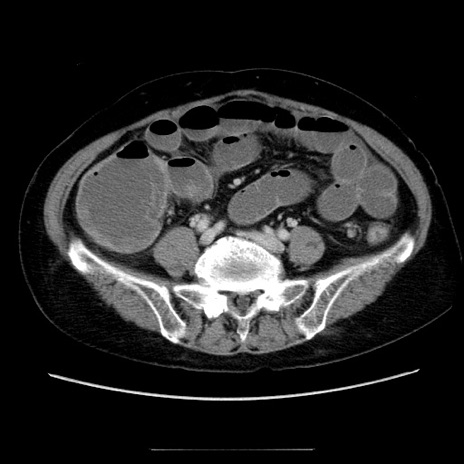

症例5(横断像)

【症例】70歳代女性

【主訴】お腹が張る

【現病歴】1週間くらい前から腹部膨満の自覚あり。昨日夜から増悪したため、本日救急外来受診。

【身体所見】意識清明、BT 36.5℃、BP 165/106mmHg、HR 80bpm、SpO2 98%、腹部:膨満、軟、自発痛・圧痛なし、触診にて不快感あり、腸蠕動音:減弱

【データ】WBC 12600、CRP 1.04